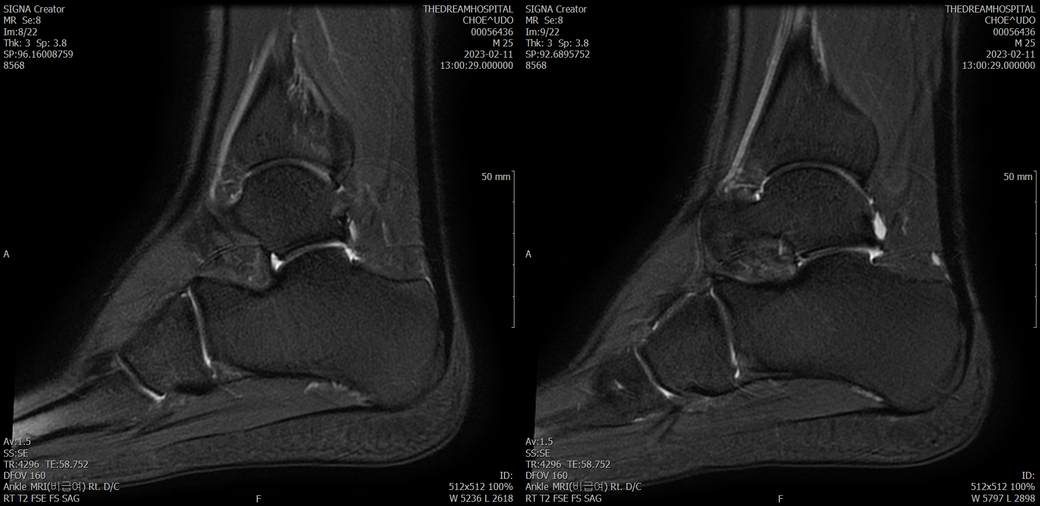

발목 mri 한번 봐주실수 있을까요?

오른발목 mri 전체사진입니다. 제가 병원을 갈수없는상황인지라.... 봐주시면 감사하겠습니다.

엑스레이에서는 문제가 없다고 하여 오른발목 mri촬영했습니다.

우선 전반적으로 봤을 때 큰 이상은 없어보입니다.

전거비인대 등도 저명한 손상은 없는 것 같아 보이지만, 어느 부분의 통증 등으로 인해 촬영을 하셨는지 말씀을 해주신다면 보다 정확한 병변파악이 가능하겠으며, 병원에서 판독이 완료되신다면 전화 등으로 문의를 해보시는 것이 좋겠습니다.